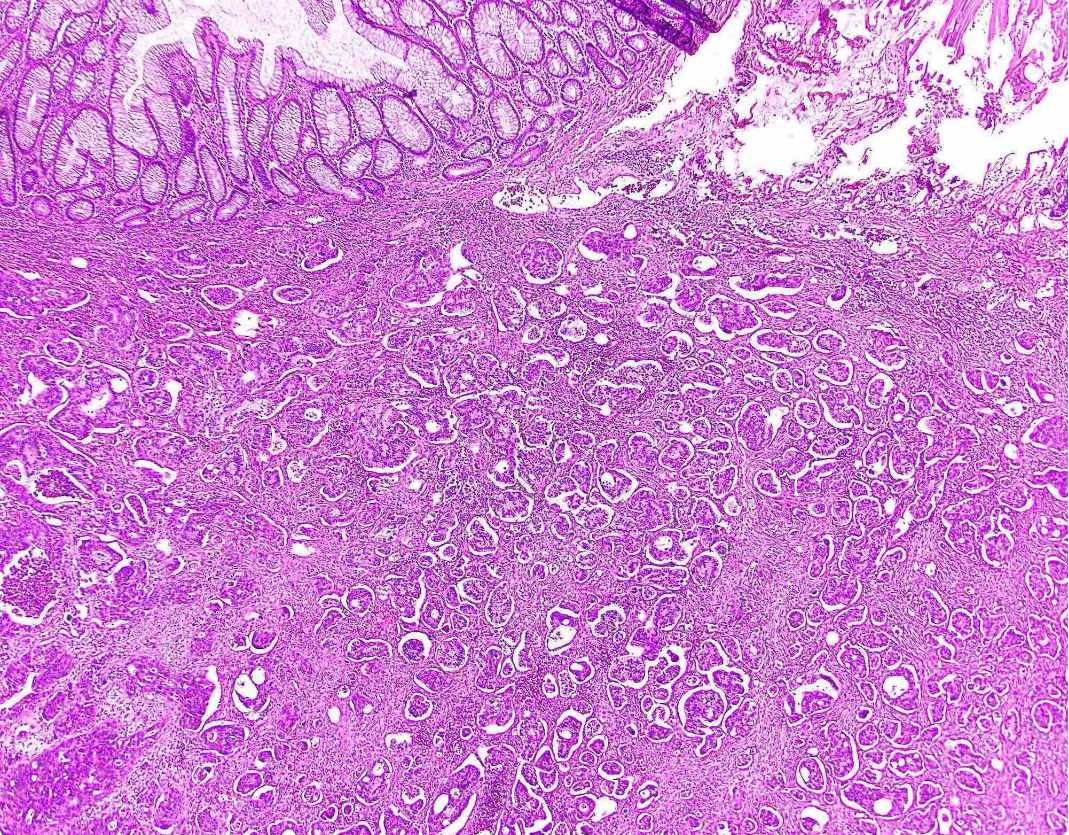

25M rectosigmoid polyp

Dx

Key features

Juvenile polyp

Key features:

Characterized by an abundance of edematous lamina propria with inflammatory cells and cystically dilated glands lined by cuboidal to columnar epithelium with reactive changes (gastric type epithelium??)

Dilated glands filled with mucus and inspissated inflammatory debris